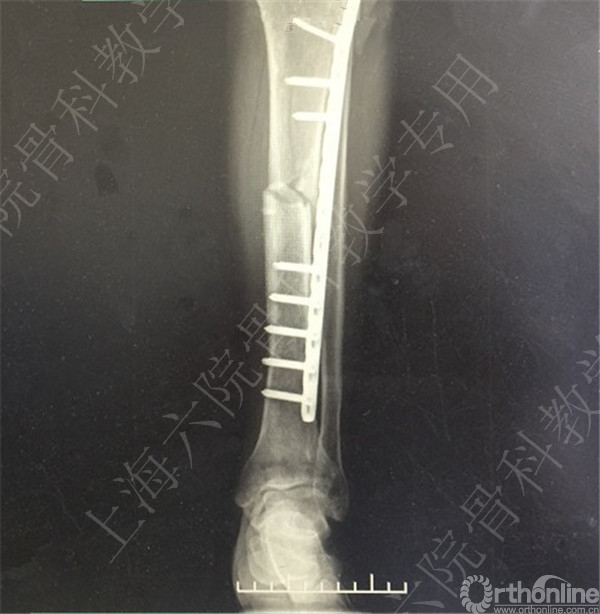

术后X线摄片示:骨折对位对线欠佳,稍成角。

患者复查,X线摄片示:骨折对位对线差,左胫骨立线欠佳,成角。

患者择期行左胫骨切开复位内固定术+髂骨异体骨植骨。

术后X线摄片示:骨折对位对线可,内固定牢靠,左胫骨对线可。

医方第一次跟换内固定术中,未纠正左胫骨立线,骨折对位对线差,未纠正成角,导致术后内固定失效,骨折成角变大。医方存在手术方式不当,手术操作不当,术后并发症观察、处理不当,对疾病评估不足,告知缺陷等过失。